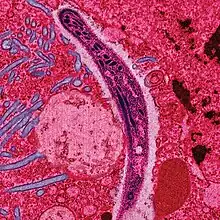

Le Plasmodium se présente sous la forme d'un protozoaire très petit (1 à 2 µm selon les formes). La coloration au May-Grünwald-Giemsa montre qu'il est constitué d'un cytoplasme bleu pâle entourant une vacuole nutritive claire et contenant un noyau rouge et du pigment brun-doré ou noir (hémozoïne).

Au début de la longue phase sanguine[140] : les mérozoïtes s'accolent aux globules rouges, les envahissent, s'y développent en trophozoïtes puis s'y divisent (schizontes).

En se diffusant, les mérozoïtes font éclater les globules rouges (c'est l'hémolyse).

L'éclatement des schizontes mûrs ou « rosaces » termine le premier cycle schizogonique érythrocytaire en libérant dans le sang, une nouvelle génération de plasmodiums, les mérozoïtes « érythrocytaires » capables de réinfecter d'autres globules rouges.

La lyse des hématies parasitées (éclatement des schizontes mûrs ou rosaces) libère de nouveaux parasites (mérozoïtes) qui contaminent à leur tour d'autres hématies. Cette destruction entraine aussi une libération des déchets du métabolisme plasmodial (pigments et débris cellulaires du globule rouge, ou hémozoïne), ces substances pyrogènes perturbent le fonctionnement de l'hypothalamus (production de cytokine comme le TNFα) et causent de fortes fièvres[143].